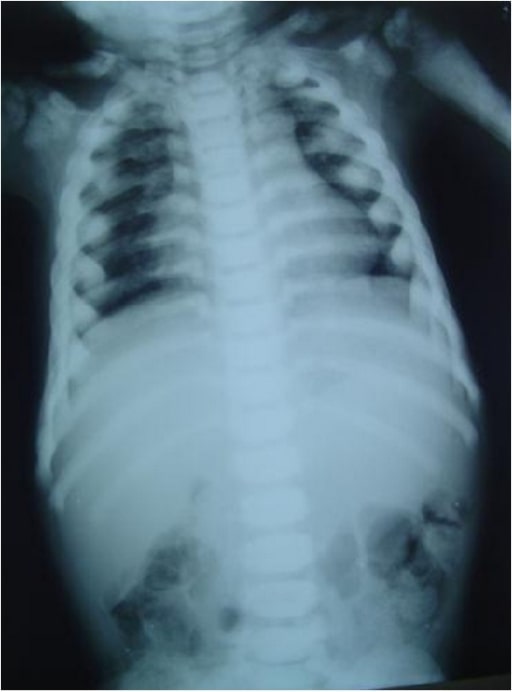

Premium Photo Xray image of human chest for a medical diagnosis Barrel Chest Medical But in people with a barrel chest, the shape of the rib cage tends to round outward and. For some people, a barrel chest is part of their natural body shape, while others develop a barrel chest over time as a result of an underlying medical condition. It usually appears in the later stages of diseases like emphysema and should. Barrel Chest Medical.